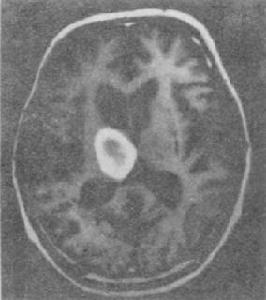

偶有顱內出血,其他臟器組織也可受累。凝血酶原活性下降到正常值的15%~20%以下時,就會發生出血,其中大部分表現為胃腸道出血。